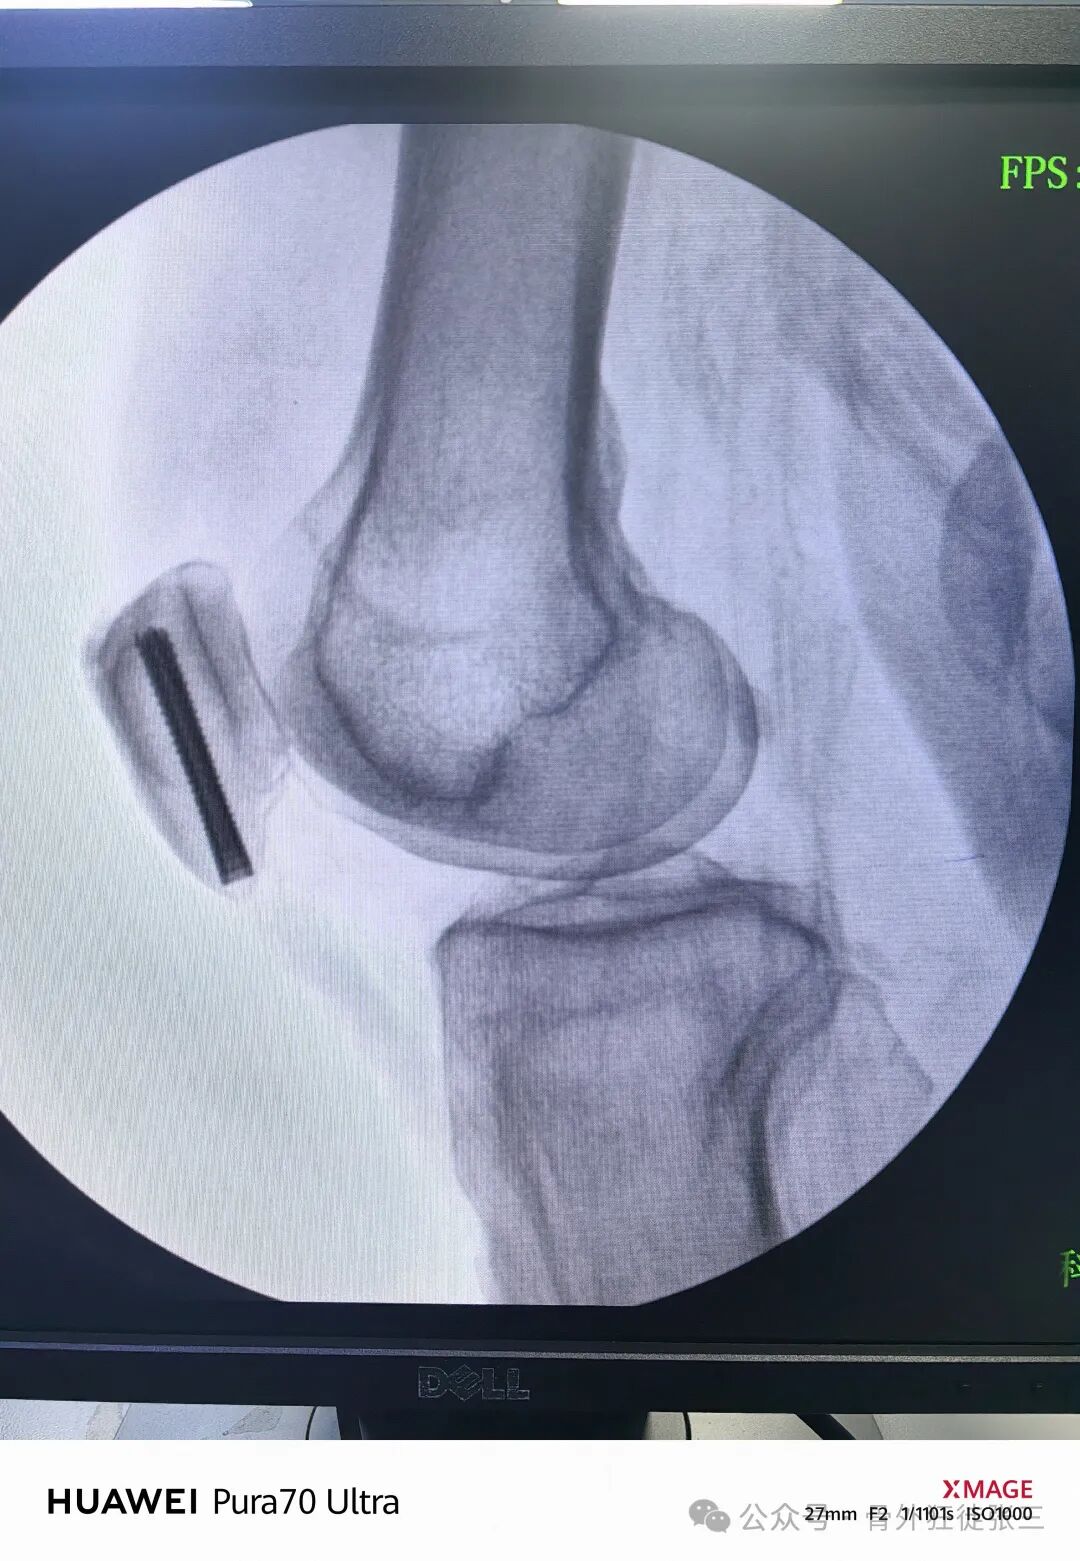

病例展示

【患者信息】:男,56岁

【主诉】:摔伤左膝关节致肿痛、活动受限2天。

【现病史及既往史】:2天前摔伤左膝关节,就诊当地医院,行石膏固定,患者无法忍受石膏固定,无法忍受卧床,要求手术治疗,早日下床,为求治疗,来院。

【临床诊断】:左髌骨骨折

【治疗经过及结果】:

0.5cm两个小切口

-

小弯钳分离到骨

20ml注射器针头定位+当做导向器

1.2mm导针从针头导向器进入

透视正位侧

打导针

空心钻钻孔后

拧入4.5mmx35mm全螺纹螺钉